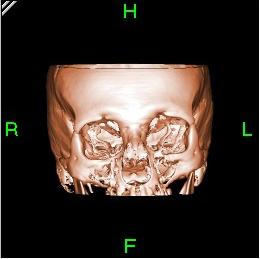

Bone reconstructed in 3D

تم تصميم الجيل الرابع مشابهًا للجيل الثالث من ناحية المسح بحركة دائرية فقط، والإضافة التي طرأت هي على الكواشف التي تم تثبيتها على كامل محيط الجانتري والتي بلغ عددها 1000 كاشف، مما جعل الحركة مقصورة على مصدر أشعة إكس فقط مع ثبات الكواشف لأنها تحيط كامل الجانتري. هذا التصميم جعل مسح مقطع كامل للجسم لا يستغرق أكثر من ثانية واحدة، وبهذه الطريقة يكون الجهاز قد صور باستخدام الأشعة السينية كل المنطقة.